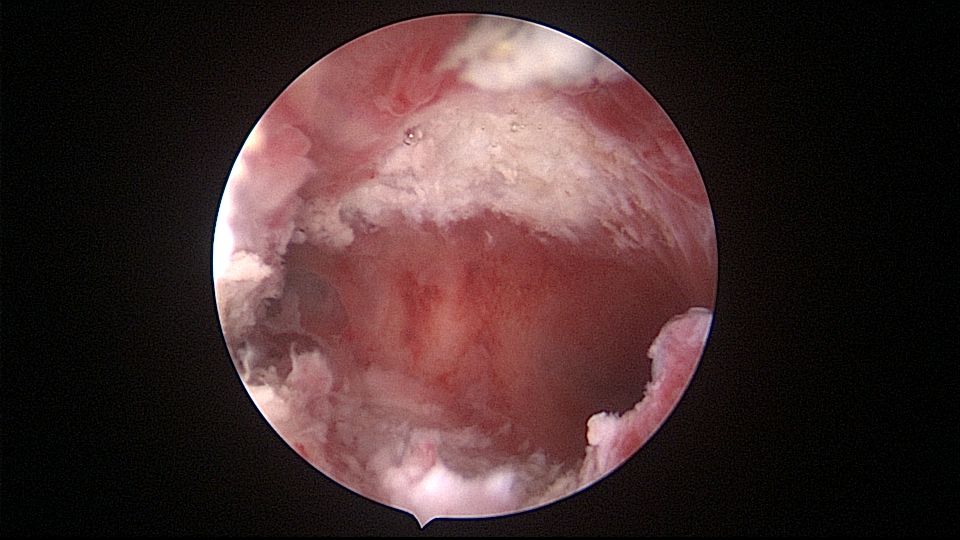

患者34岁,G4P1,顺产1次,继发不孕,宫腔容积小,宫腔粘连。2020年9月宫腔镜探查,见宫腔下段幕状粘连,两侧小孔与宫腔上段相通,形成假的输卵管开口。双极电针切开粘连,宫腔形态恢复正常,显露双侧输卵管正常开口。2020年10月宫腔镜二探取球囊,宫腔形态正常,双侧输卵管开口可见。2021年6月自然妊娠,2022年2月足月剖宫产分娩,2023年5月再次妊娠1次,人流终止妊娠。现39岁,G6P2,顺产1次,剖宫产1次。